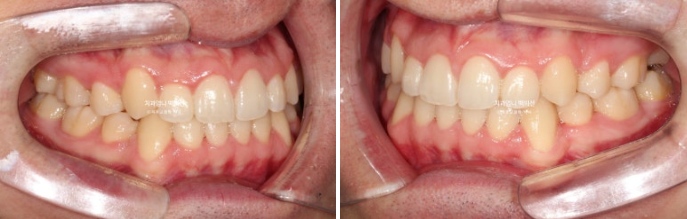

22.09~25.04

안모 전 후 보겠습니다.

아랫입술이 뒤로 들어가며 입술 밸런스가 좋아졌습니다.